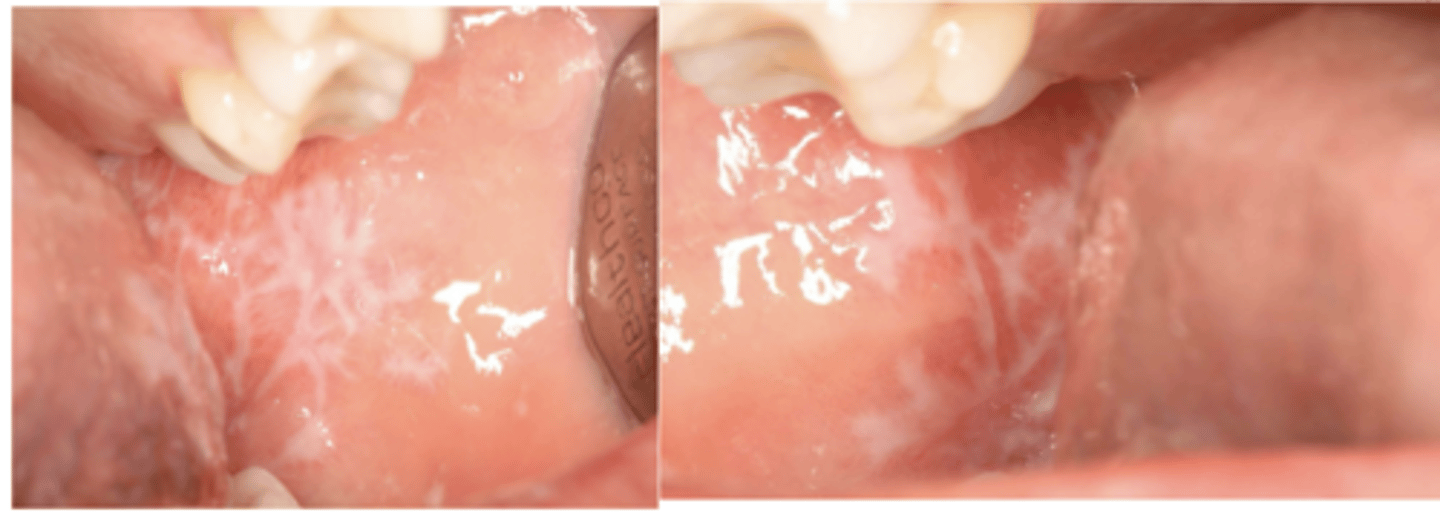

lichen planus (reticular)

What condition?

- Often asymptomatic

- Posterior buccal mucosa (bilaterally)

- Lacy white striations (Wickham striae)

Wickham striae (lacy white striations) is a classic feature of what condition?